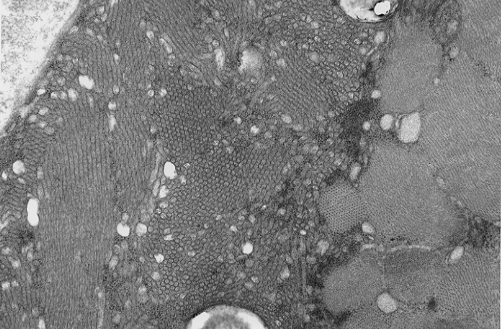

Pathology of the case: On hematoxylin-eosin stained frozen sections, there are many stongly basophilic, irregular subsarcolemmal depositions (Panel A and B). There is no significant variation in fiber diameter, increase in centrally located nucleus, inflammation, necrotic fiber, regenerating fibers or target fibers. These deposits appear bright red on modified Gomori's trichrome (Panel C). On ATPase reaction at pH 4.6 (dark fibers are type 1, pale fibers are type 2a while intermediate-intensity fibers are type 2b), there is no fiber type predominance (Panel D). Although the deposits are not visualized in the ATPase preparation, they are strongly reactive in NADH-TR reaction. Intesestingly, these deposits are not visualized in another preparation of oxidative enzyme- succinate dehydrogenase (Panel F). On the adenylate deaminase preparation, these deposits are strongly reactive (Panel G). The subsarcolemmal deposits are well visualized under the electron microscope which is electron dense (Panel H). On cross sections, these deposits are bundles of densely packed polygonal to round tubules with double walls that are arranged in small fascicles (Panel  I and J). The tubules are about 50-80 nm in diameter. The tubular aggregates also arrange in longitudinal bundles that run along the myofibrils (Panel K).

On resin embedded semithin sections, tubular aggregates may measure over 40 mm in length on longitudinal sections. At the ultrastructural level, tubular aggregates appear as masses of bundles of long, straight, parallel tubules in between myofibrils especially beneath subsarcolemmal locations. They are often double barrel and contains an inner tube but they may be up to eight inner tubes. The outer tube is usually about 50 nm in diameter but may be as large as 80 nm. The inner tubules are 20-30 nm in diameter.